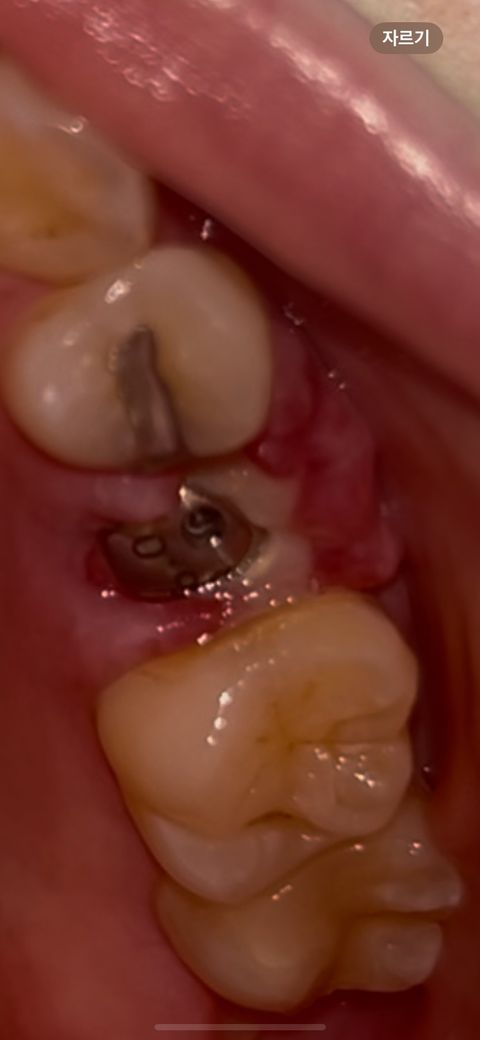

임플란트 뼈이식하고 나사도 심고 12일 지났어요 실밥 푼 지 4일? 지났고 양치하고 보니 잇몸 주위가 하얀색이네요 ㅠㅠ 문제 생긴걸까요

고리식을 할 때 멤브레인 등을 쓰는 경우가 있습니다. 이런 멤브레인 등은 외부로 노출되었을때 하얀색으로 보일 수 있습니다.

가능하면 외부로 노출되는 것이 좋은 것은 아니나 해당 부위를 자극하지 않아 준다면 잇몸이 위로 자라 올라오게 됩니다. 자세한 확인을 위해서 치과에서 진료를 받아보세요.